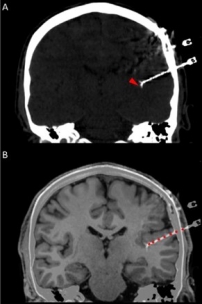

In addition to the very valuable iEEG recordings from the clinical macroelectrodes, our iEEG recordings also include signals recorded with microelectrodes. The additional microelectrodes have a diameter of about 40 μm (smaller than the hair) and spread out of the tip of the clinical intracranial electrode. They are added solely for research purposes and, because of their small size, they can record the electrophysiological firing activity generated by nearby individual neurons. We analyze this data by using algorithms which classify the different waveforms recorded by a single microwire into action potentials generated by different neurons. We also use population decoding methods to extract the information associated by the neurons (e.g. “concept” neurons which preferably fire in response to specific images of the same individual). To localize the site of the macro- and micro-electrodes with high spatial resolution, we combine post-implantation CT scans with pre-implantation neuroimaging scans from the 7-Tesla MRI, available at the University of Magdeburg.

|

4. © Carlson et al., 2018. Reproduced according to the terms of Creative Commons Attribution License. Carlson, April A., Ueli Rutishauser, and Adam N. Mamelak. 2018. “Safety and Utility of Hybrid Depth Electrodes for Seizure Localization and Single-Unit Neuronal Recording.” Stereotactic and Functional Neurosurgery 96 (5): 311–19. https://doi.org/10.1159/000493548.